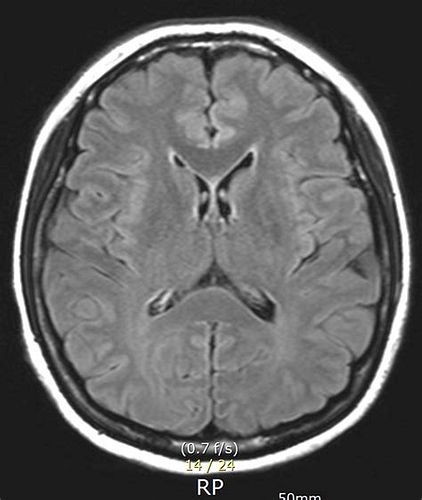

뇌 MRI (자기공명영상) 검사

MRI 검사 비용

- 비급여(보험 미적용) 기준

- 일반적으로 35만~70만 원 선에서 많이 책정됨.

- 대학병원, 대형병원: 50만~70만 원, 일부는 100만 원까지도 가능.

- 지역 중소병원, 의원: 35만~50만 원 수준.

MRA 검사 비용

MRI + MRA 동시 검사

- 동시 촬영 시 60만~100만 원(비급여), 보험 적용 시 30만~50만 원 수준.